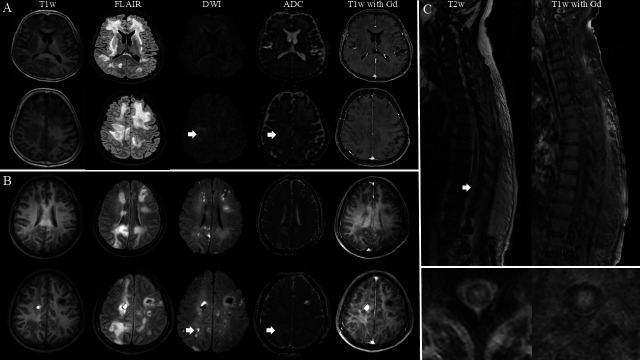

目的:本研究旨在阐明伴有神经系统受累的血管内大B细胞淋巴瘤(IVLBCL)患者的临床表现、实验室检查结果和转归,并对伴有和不伴有神经系统受累的IVLBCL进行鉴别。方法:2005年1月至2024年9月在泰国玛希隆大学Siriraj医院进行队列研究。分析临床资料、实验室值及中枢神经系统影像学结果。分类变量使用χ 2或Fisher精确检验进行比较,而连续变量则酌情使用Mann-Whitney U检验进行分析。结果:30例IVLBCL患者中,10例有神经系统受累,20例无神经系统症状,包括脊髓病(5例,50%);认知障碍(3例,30%);癫痫发作(2例,20%);视神经病变、偏瘫、同义性偏视、眩晕、全身性失语(各1例,占10%)。60%伴有神经系统受累的IVLBCL有全身性症状,包括持续发热、贫血、厌食和体重减轻。MRI表现为幕上、幕下及脊髓高强度病变,突出表现为纵向广泛的脊髓病变(4例,40.0%)。伴有神经系统受累的IVLBCL的中位生存时间为4.1个月(95% CI: 0.0 ~ 17.1个月),1年生存率为37.5%,2年生存率为25.0%。解释:本研究强调了伴有神经受累的IVLBCL的独特临床、实验室特征和影像学特征,并将其与无神经受累的IVLBCL进行了比较。尽管IVLBCL具有侵袭性,但早期识别这些发现对于准确诊断和改善患者预后至关重要。

Results: Of the 30 patients with IVLBCL, 10 had neurological involvement and 20 without neurological symptoms, including myelopathy (5 patients, 50%); cognitive impairment (3 patients, 30%); seizures (2 patients, 20%); optic neuropathy, hemiparesis, homonymous hemianopia, vertigo and global aphasia (each affecting 1 patient, 10%). 60% of IVLBCL with neurological involvement had systemic symptoms, including prolonged fever, anaemia, anorexia and weight loss. MRI showed hyperintense lesions in the supratentorial, infratentorial and spinal cord with the prominent findings being longitudinally extensive cord lesions (four patients, 40.0%). The median survival time of the IVLBCL with neurological involvement was 4.1 months (95% CI: 0.0 to 17.1 months), with a 1-year survival rate of 37.5% and a 2-year survival rate of 25.0%.